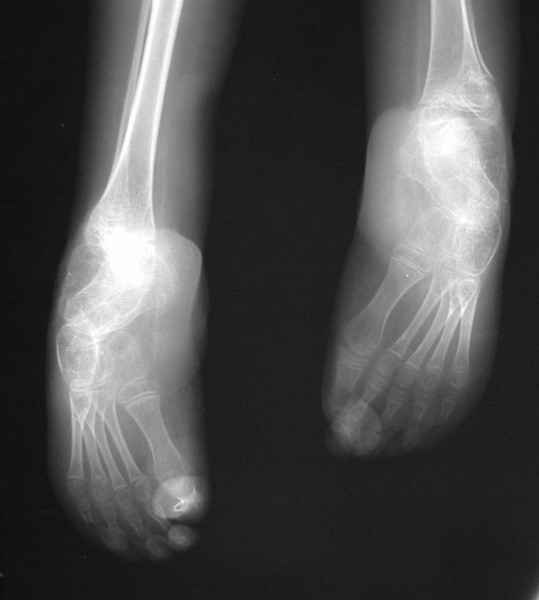

Диагноз. Артрогрипоз. Врожденные двусторонние вывихи бедер. Рецидивирующая двусторонняя врожденная косолапость тяжелой степени (состояние после оперативной коррекции в 2004 году с обеих сторон). Мягкотканные разгибательные контрактуры коленных суставов. Атрофия мышц голеней. Значительное нарушение функции нижних конечностей.

С раннего неонатального периода находится под наблюдением травматолога по месту жительства по поводу врожденной кривошеи (?), вр. вывихов бедер, вр. двусторонней косолапости, получал лечение у травматолога в ОТКБ - на стационарном лечении находился 14 раз с диагнозом: Артрогрипоз с поражением всех крупных суставов нижних конечностей. Лечился консервативно, проводились закрытые вправления бедер, коррекция косолапости, наложение гипсовых повязок. В возрасте 6 лет (2004) мальчику выполнена оперативная коррекция врожденной косолапости: слева - ахиллопластика, справа - операция Зацепина. Дальнейшее наблюдение и лечение ребенок получал по месту жительства. Постепенно стопы приняли прежнее положение (эквино-варусное), мальчик перестал ходить, мама носит его на руках, обучение по общеобразовательной программе ребенок получает на дому индивидуально.

Место болезни. Передвижение ребенка резко нарушено, нижние конечности имеют атрофированный вид, мышцы голени дряблые, истончены. Форма всех суставов нижних конечностей деформирована. Коленные и тазобедренные суставы в положении разгибания. Сгибание и разведение тазобедренных суставов резко ограничено, имеет место их выраженная приводящая контрактура. Сгибание коленных суставов возможно до 90 , но при этом отмечаются болевые ощущения. Со слов мальчика: он боится сгибать коленные суставы из-за имевших место болезненных подвывихов голеней кнаружи. Клинически определяется невыраженная нестабильность коленных суставов - патологическая подвижность кнаружи (больше слева). Правая нижняя конечность короче левой на 8 см. Скарповские треугольники расширены. Ягодичные области симметричные. Ромб Михаэлиса симметричен, Явной деформации позвоночника не выявлено (в положении лежа и сидя). Оба коленных сустава деформированы, незначительно вальгированы (до 10 ), сгибание их резко ограничено. Стопы и голеностопные суставы деформированы, имеются п/о рубцы цвета кожи по задней и внутренней поверхностям голеностопных суставов и стоп. Сохраняется выраженное эквиноварусное положение обеих стоп, выведение их в правильное положение не возможно: приведение передних отделов стоп до 45 , супинация 45-50 , эквинус более 90 , движения качательные.